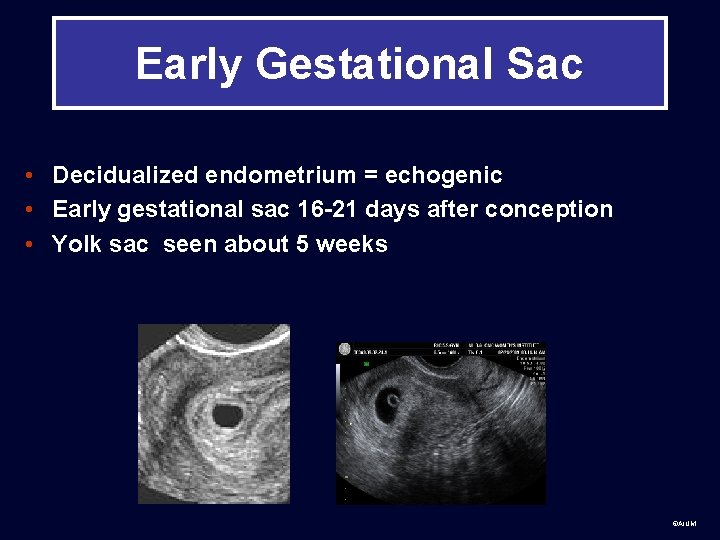

Early Gestational Sac • Decidualized endometrium = echogenic • Early gestational sac 16 -21 days after conception • Yolk sac seen about 5 weeks ©AIUM